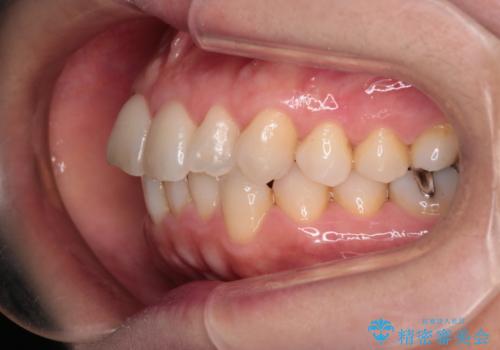

【インビザライン 】前歯のガタガタを治したい

- 前歯のガタガタを主訴に来院されました。

インビザライン で治療しました。途中は使用時間が20時間を切ることもありましたが、それでも頑張って使っていただき1年半で矯正終了することができました。